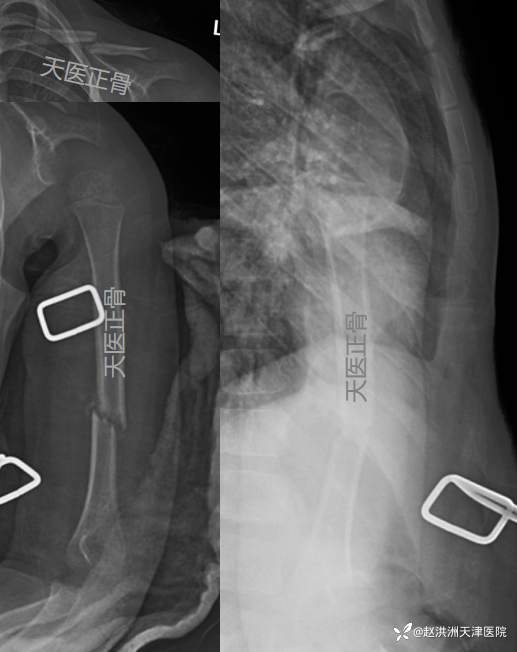

伤后6个月,骨折痕迹几乎消失

1. 儿童和青少年锁骨骨折的主要治疗方法为非手术治疗,即便存在明显的移位,非手术治疗也可使骨折在原位形成骨痂并愈合,且功能预后良好。

2. 绝大多数儿童肱骨干骨折可采用保守治疗方法,因上肢骨骼是非负重的,其功能恢复不需要严格解剖复位,此外肩、肘关节的活动及前臂旋转都可以代偿轻度到中度的肱骨畸形。对于骨骼未发育成熟的儿童患者,肱骨有着很强的畸形塑型能力。一般≤30°内翻畸形,≤20°后成角,≤15°内旋畸形及1-2cm的短缩移位都是可以接受的畸形(选自第八版《洛克伍德·威尔金斯 儿童骨折》)。